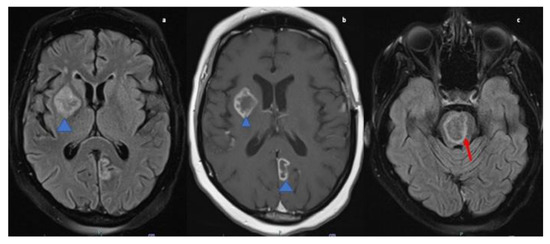

A 47-year-old African American female with past medical history of hypertension was transferred from an outside hospital after presenting with left sided upper and lower extremity weakness., MRI brain was performed which demonstrated multiple ring-enhancing lesions on post contrast T1 images, the largest within the right basal ganglia and the pons. There was also a smaller lesion in the left medial occipital lobe (refer Figure 4. The findings were concerning for possible demyelinating disease such as tumefactive multiple sclerosis, metastases or infection. A CT chest, abdomen, and pelvis revealed uterine masses likely representing uterine fibroids but otherwise no evidence of malignancy. Subsequently MRI of the pelvis was performed for further work up of the uterine masses which showed the large heterogeneous uterus was most likely due to degenerative fibroids and no suspicious uterine lesion was seen. Lumbar puncture was not performed due to concern for increased ICP. TTE was performed to rule out infective endocarditis and showed no evidence of valvular vegetations. Autoimmune and infectious serum panel were all negative.

Figure 4.

MRI Brain axial fluid-attenuated inversion recovery (FLAIR; (a)) & T1-weighted post contrast image (b) reveals hyperintense lesion in right gangliocapuslar region (blue arrowhead; (a)) with corresponding heterogenous peripheral ring enhancement, in addition to enhancement in the left paramedian occipital lobe (blue arrow head; (b)). FLAIR image (c) reveals circumscribed intra-axial parenchymal lesion in the pons (red arrow).

A brain biopsy was performed and final pathology showed necrotizing granulomas with associated calcifications consistent with NS. Biopsy stains for acid-fast and fungal (methenamine silver and PAS) organisms, with appropriate positive controls, were performed and were negative. A Congo red stain, with an appropriate positive control, was also performed and was negative. The patient was started on methylprednisolone 1 g daily for a total of five days. At the time of discharge the patient was switched to prednisone 60 mg daily for a total of 30 days and advised to follow up in the neurology clinic in four weeks after discharge. The patient reported an improvement in the left sided weakness on his follow-up visit. In addition to prednisone 60 mg daily, the patient was prescribed omeprazole 20 mg daily and advised to continue with home medications (refer Table 1).

MRI brain and orbits revealed an enhancing left cerebellar nodule with surrounding abnormal hyperintense signal on FLAIR extending to the cerebellar peduncle. Mass-like enhancement of the folia surrounding the nodule was also noted. MRI orbits showed bilateral smooth optic nerve sheath enhancement without abnormal signal within the optic nerves. There were also imaging findings concerning for papilledema with flattening of the posterior globes (refer Figure 5) and T2 images (not shown) also demonstrated intraocular protrusion of the optic nerve heads. These findings were most consistent with inflammatory processes such as sarcoid or possible leptomeningeal metastatic disease.

Figure 5.

MRI orbit axial T1-weighted fat-suppressed post contrast image (a) and coronal (b) images reveal enhancement of bilateral optic nerve sheaths (red arrow). MRI Brain axial fluid-attenuated inversion recovery (FLAIR) (c) image reveals ill-defined patchy parenchymal hyperintensity in the left cerebellar hemisphere extending to the cerebellar peduncle (blue arrowhead).

A lumbar puncture was performed, and a VP shunt was placed. CSF analysis revealed CSF protein of >400 mg/dL, elevated opening pressure, CSF ACE mildly elevated at 3.7 U/L (normal up to 2.5), 12 WBC predominant lymphocytic 90%, and negative meningitis panel. Serum ACE was normal. CT chest/abdomen/pelvis were without evidence of malignancy or systemic sarcoid.

The patient received left optic nerve sheath fenestration in an effort to decrease the swelling of the optic nerve. Biopsy of the left optic nerve sheath demonstrated findings concerning for NS. The patient was started on one dose of cyclophosphamide with Mesna and discharged with oral tapering prednisone starting at 60 mg dose, with a follow-up scheduled in neurology and ophthalmology clinics. Following the treatment, the patient continued to have lack of light perception in left eye but the visual acuity improved within the right eye to 20/40. Recommendation was to follow-up with the neurology outpatient clinic (refer Table 1)

Non-specific MRI findings such as periventricular white matter lesions, meningeal enhancement, brain parenchymal lesions, dural mass lesions, and spinal cord involvement are commonly reported in NS [1,34,35]. However, ring-enhancing lesions, though reported rarely, may be the only presentation of NS [36,37]. Case four presented with increased intracranial pressure due to cerebral vasogenic edema and multiple ring-enhancing lesions adding neoplastic lesions, demyelinating diseases, contusions, and Wegner’s granulomatosis to the differential list. Such a case poses unique challenges in diagnosis as many of the differentials cannot be excluded immediately because of inability to perform LP in the presence of cerebral edema. However, whole-body imaging narrowed down the diagnosis of NS and it was confirmed by biopsy.

The presenting symptoms of case five were retro-orbital pain, blurring of vision progressively leading to complete diminution and fundoscopic examination revealing papilledema consistent with increased ICP. However, cerebellar and cervical leptomeningeal enhancement were also discovered on MRI, and the patient exhibited no symptoms from these lesions. Hence, it appears that in some cases of NS the imaging findings may not correlate entirely with the clinical presentation of the disease.